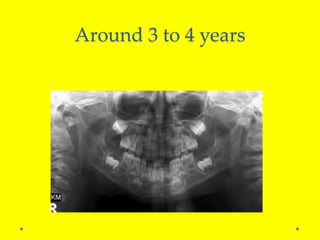

Around 3 to 4 years

Around 3 to4 years